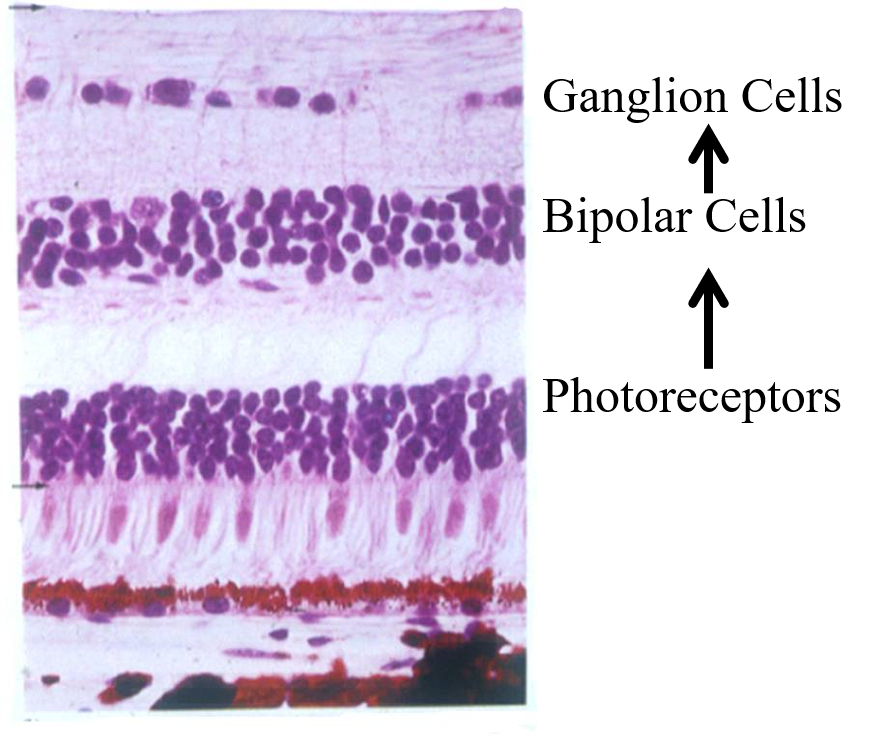

What is this?

A cross section of the retina.

[you should be able to label the cross section]